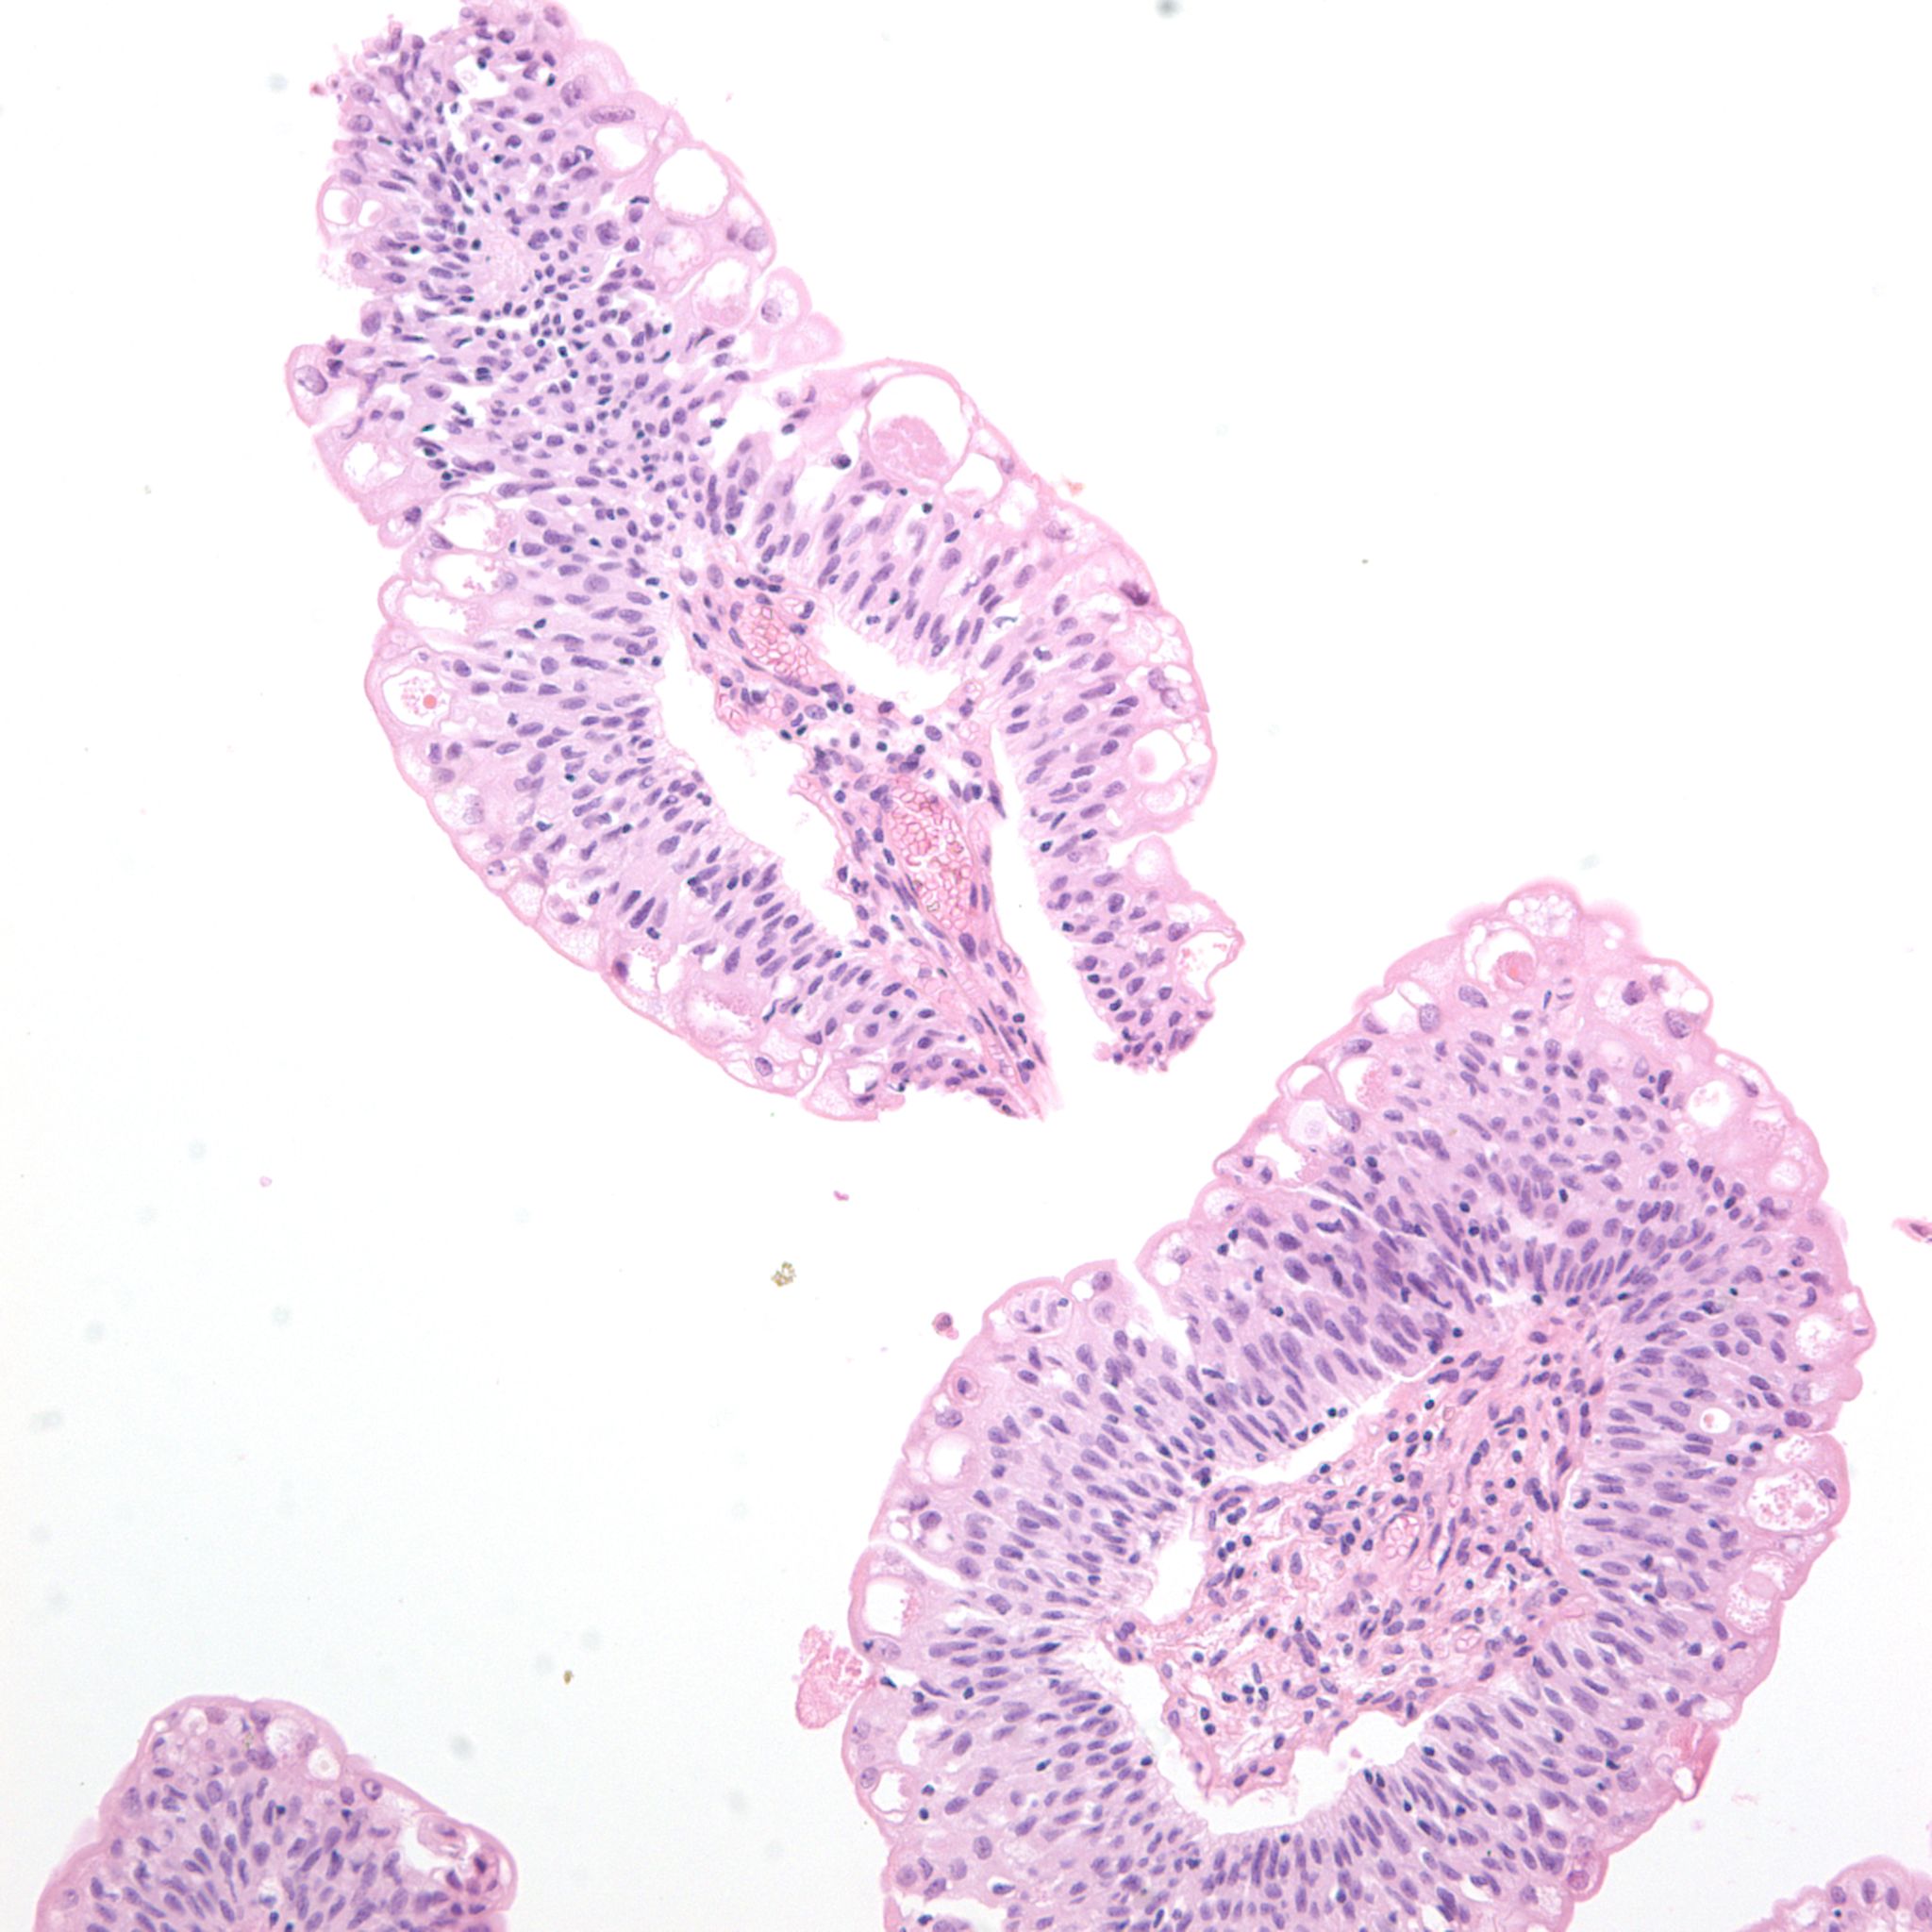

Bladder Papillary Lesions

Case ID: 303